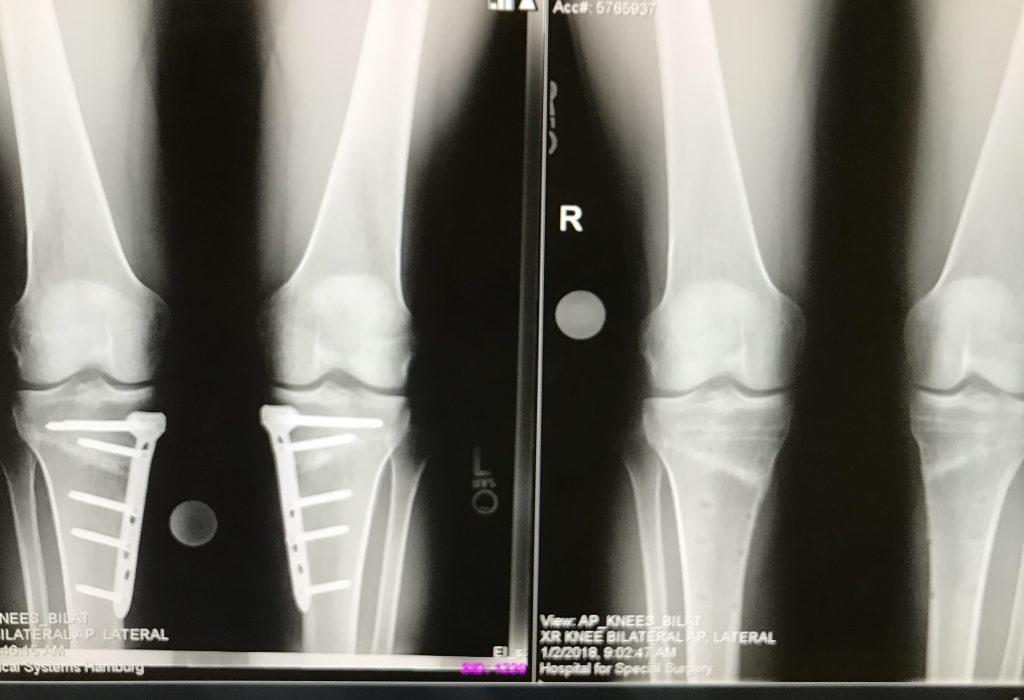

I went to see Dr. Rozbruch at HSS who explained he could treat the condition with a less invasive surgery and properly align my legs. I underwent a bilateral osteotomy to straighten my bowlegs - the left leg in October of 2016 and the right leg 7 weeks later in December. With the consent and encouragement of Dr. Rozbruch and despite being on crutches, within 3 weeks of surgery I was in the pool. Four weeks after the second surgery I was on the spin bike.

I completed a one day Rim to Rim hike of the Grand Canyon in September 2017 and ran my first race about 1 year after surgery, in December of 2017. The race was a half marathon and I was able to run at a 6:33 pace for 19th place overall. While it wasn’t a record time for me I had minimal discomfort and at this point I still had plates in my legs.

Dr. Rozbruch removed the plates in an outpatient procedure in mid-December 2017, and after a few weeks of rest, I resumed running and cycling. On 5/19/2018 I ran another half marathon at a 6:22 pace, with no discomfort. I look forward to continuing to train for running and cycling events in the future.